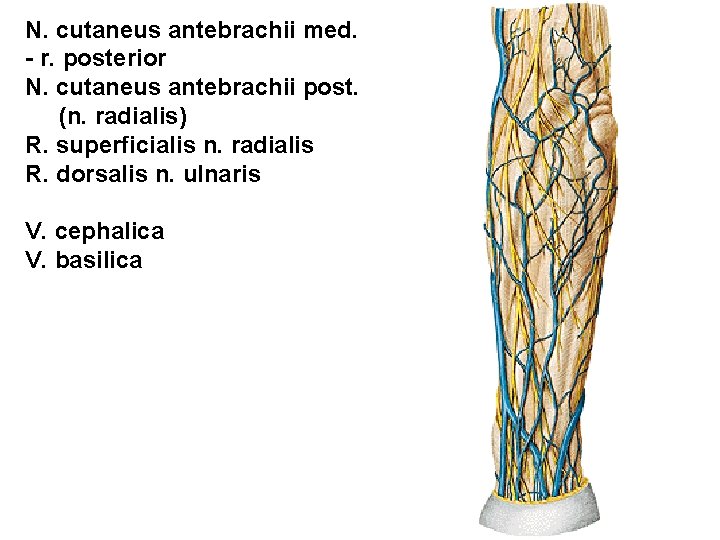

N. cutaneus antebrachii med. - r. posterior N. cutaneus antebrachii post. (n. radialis) R. superficialis n. radialis R. dorsalis n. ulnaris V. cephalica V. basilica